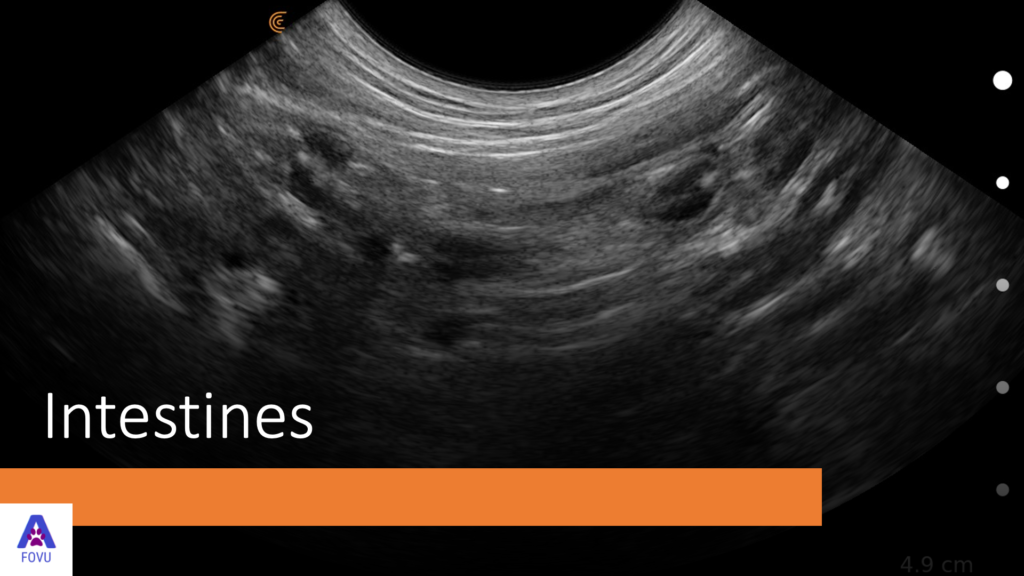

“In the image above we’re looking at one loop of the small intestine. The layers we see here and on the other side are as follows:

Serosa – is the first layer at the top shown as a thin white line

Muscularisis – is the next hypoechoic line

Submucosa – is the following hyperechoic line

Mucosa – is thicker and hypoechoic

Lumen – is in the middle and can be filled with gas, which will obstruct the view of the other side wall.

Note: It’s wise to know the animal’s diet whether they’re raw fed or if they’re kibble fed as you’ll get different images. You might find fluid or mucus as you see here. When we get down to the colon, you’ll find feces.”